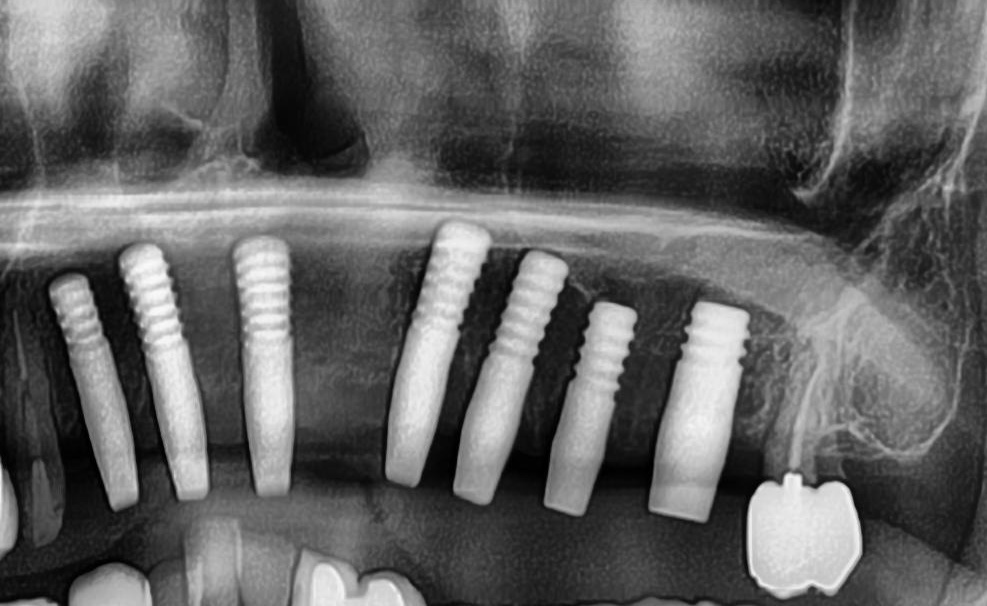

開けた穴に、専用道具を使ってネジを締めるように長さ2センチ程のインプラントを骨に埋め込んでいきます。

続けて、その他の部位も同じ工程で植立を行いました。

インプラントオペでは、隣り合う歯にインプラントを植立する場合でも、複数本同時に進行することはせず1本ずつ同じ工程を繰り返して植立します。

しっかりとインプラント埋め込まれた後は、動揺がないか、噛んだ時に当たらないかなどを確認して、最後にパノラマ写真を撮影して今回のオペは終了となりました。